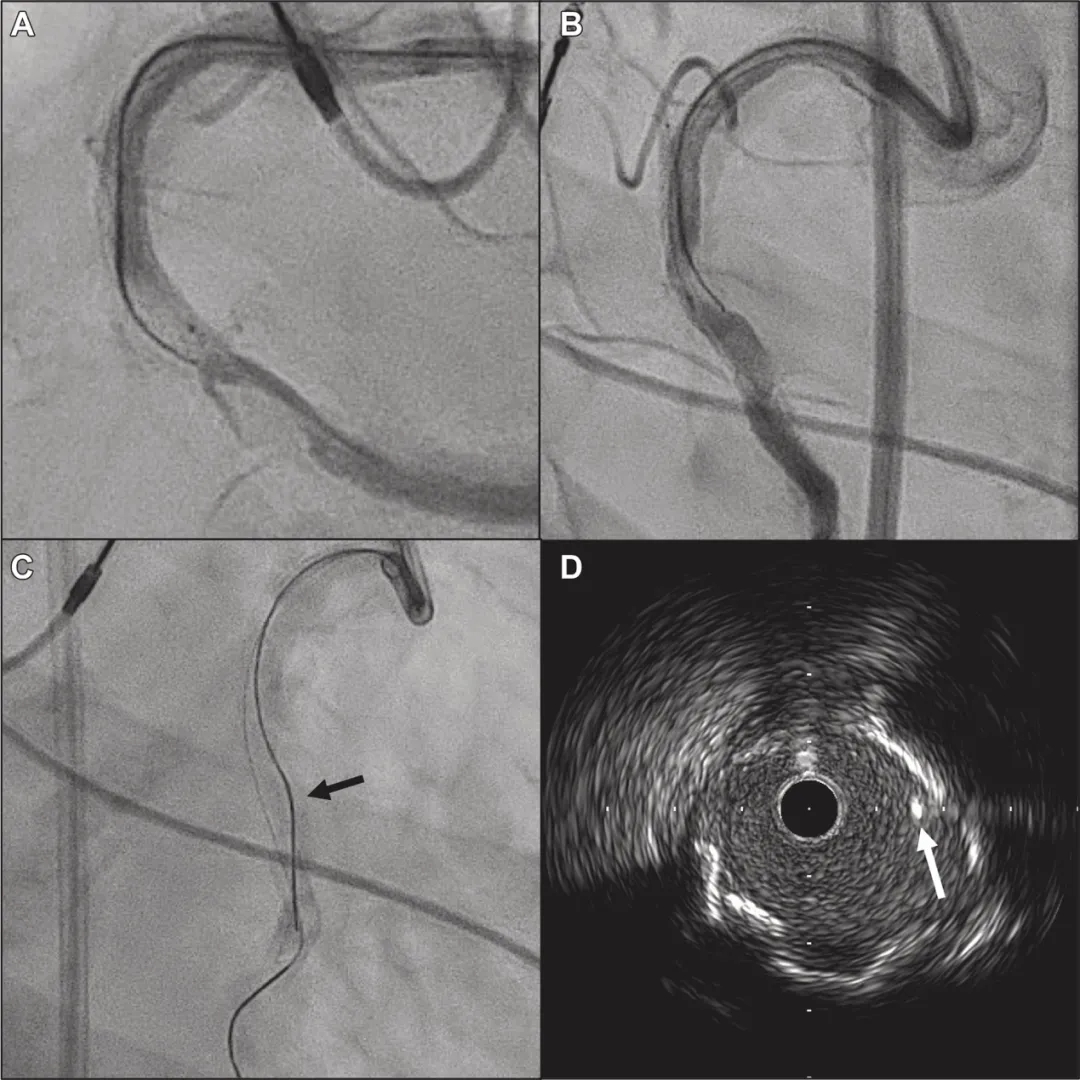

更换导丝,在实时IVUS引导下使用Gaia Next 4(GN4,ASAHI INTECC)再次穿刺钙化结节。GN4沿类似CP12ST的路径进入钙化结节,最终通过3D导丝技术成功穿出钙化结节并返回残余真腔(图5)。1.5mm球囊预扩后,IVUS提示GN4创建的新通道位于钙化结节中心(图6A)。再经1.75mm旋磨头行旋磨术及3.25mm刻痕球囊追加扩张后,IVUS确认实现理想的同心性扩张及急性管腔获得(图6)。植入3.5mm药物洗脱支架,最终造影显示冠状动脉血流充足且无并发症(图6)。

图5 GN4的冠状动脉造影及IVUS图像

(A)左前斜位显示GN4接近远端残余真腔。

(B)右前斜位显示GN4头端几乎接触远端残余真腔。

(C)GN4穿过钙化结节进入远端残余真腔(黑箭头:GN4)。

(D)通过钙化结节后,GN4与SION blue导丝及IVUS导管位于同一管腔(白箭头:钙化结节杆部)。

图6 导丝通过后冠状动脉造影及IVUS图像

(A)GN4穿过钙化结节中心。

(B)1.75mm旋磨头通过病变。

(C)旋磨术及3.25mm刻痕球囊扩张后形成多处裂隙(白箭头:裂隙)。

(D)3.5mm依维莫司支架完全扩张。

(E、F)多角度造影显示钙化结节病变完全扩张。